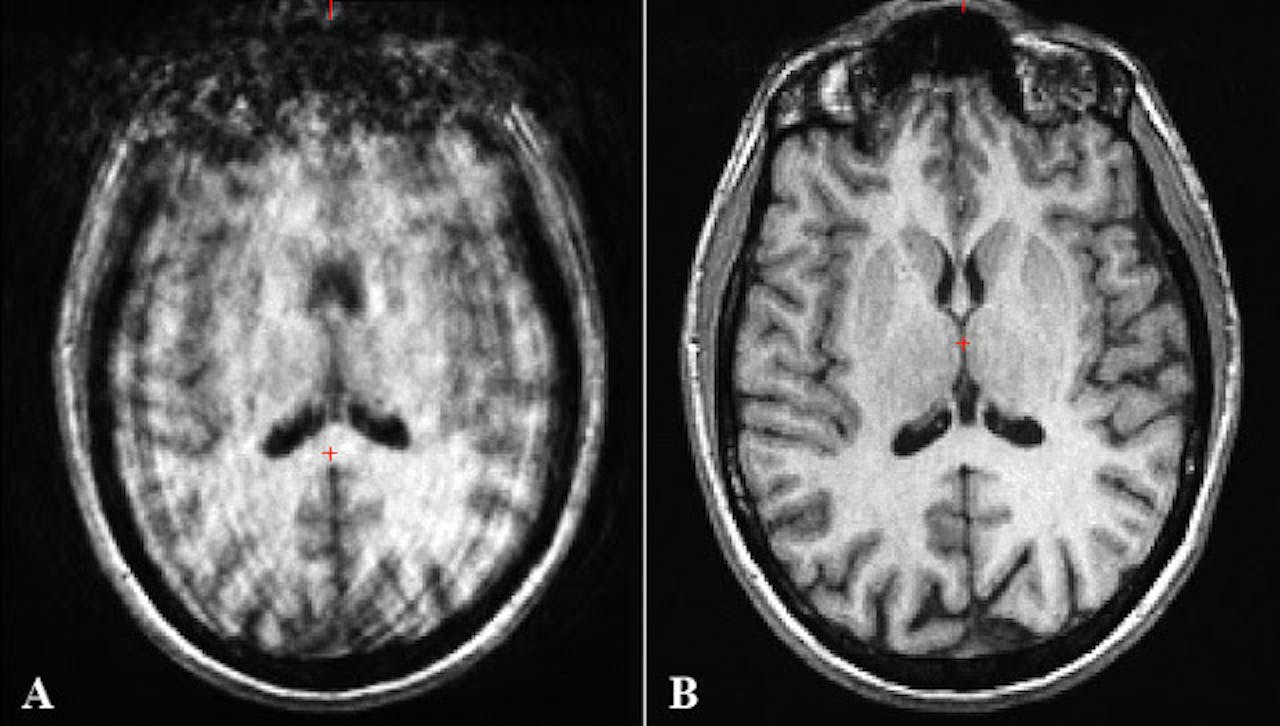

Beweging heeft ontzettend veel invloed op de kwaliteit van hersenscans (zie plaatje hieronder), waardoor jouw statistische model helemaal niet de neurale verschillen bij ADHD oppikt, maar simpelweg gebaseerd is op het verschil in beweging!

Beweging heeft ontzettend veel invloed op de kwaliteit van hersenscans

Do Tromp, A guide to quantifying head motion in DTI studies,The Winnower 3:e146228.88496 (2016) CC BY 4.0Dit soort onverwachte invloeden, zoals beweging bij ADHD-onderzoek, noemen we in de wetenschap verwarrende variabelen’ (in het Engels: confounds). Deze confounds zorgen ervoor dat je stiekem helemaal niet meet wat je denkt dat je meet. Met andere woorden, in dat geval is meten helemaal niet weten! En dit kan een groot probleem zijn.